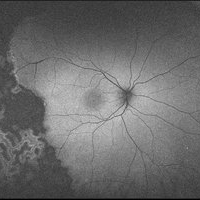

Wyburn Mason Racemose Angiomatosis

Color fundus montage of an 13-year-old female with arteriovenous malformation (Wyburn Mason Racemose Angiomatosis) affecting her right eye. The retinal arteriovenous malformation appears to be stable. She presented with NLP in the eye, strabismus, and peripheral retinal ischemia. She is at risk for neovascular complications; however, she is currently being treated with Sirolimus. Since she is on this systemically, there is no need to perform intraocular anti-VEGF injections or PRP laser. She also presented with optic atrophy affecting her left eye, secondary to chiasmal involvement of arteriovenous malformation. She has had a potential progressive visual field loss involving the temporal aspect of her visual field from the left eye. There is sector optic atrophy. Presumably, this is due to a compressive effect of her arteriovenous malformation on the nasal nerve fiber layer (corresponding to the temporal visual field) crossing to the right occipital cortex at the chiasm.

Photographer: Olivia Rainey

Imaging device: Topcon 50dx

Condition/keywords: arteriovenous malformation, color fundus photograph, color photo, montage, peripheral ischemia, Sirolimus